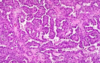

Describe the histological appearance of the thyroid gland.

- Arranged into follicles with a small amount of stromal tissue between them

- They are lined by epithelial cells and have a large amount of colloid in the middle

- Parafollicular cells are found between the follicles